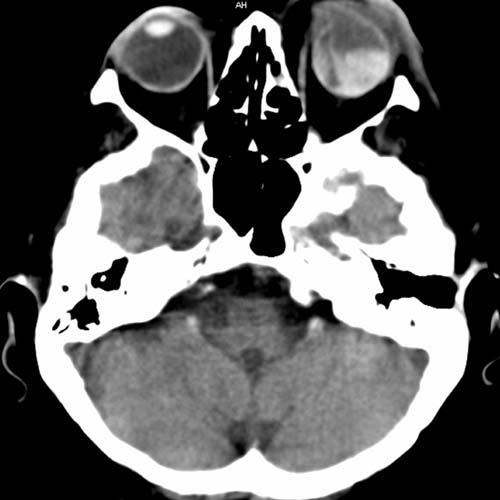

61-jähriger Diabetiker mit Visusverlust auf dem linken Auge. Patient sieht auf dem linken Auge verschwommen

CCT nativ (ohne Kontrastmittel). Im Seitenvergleich

hyperdenser Glaskörper links.

Glaskörperblutung